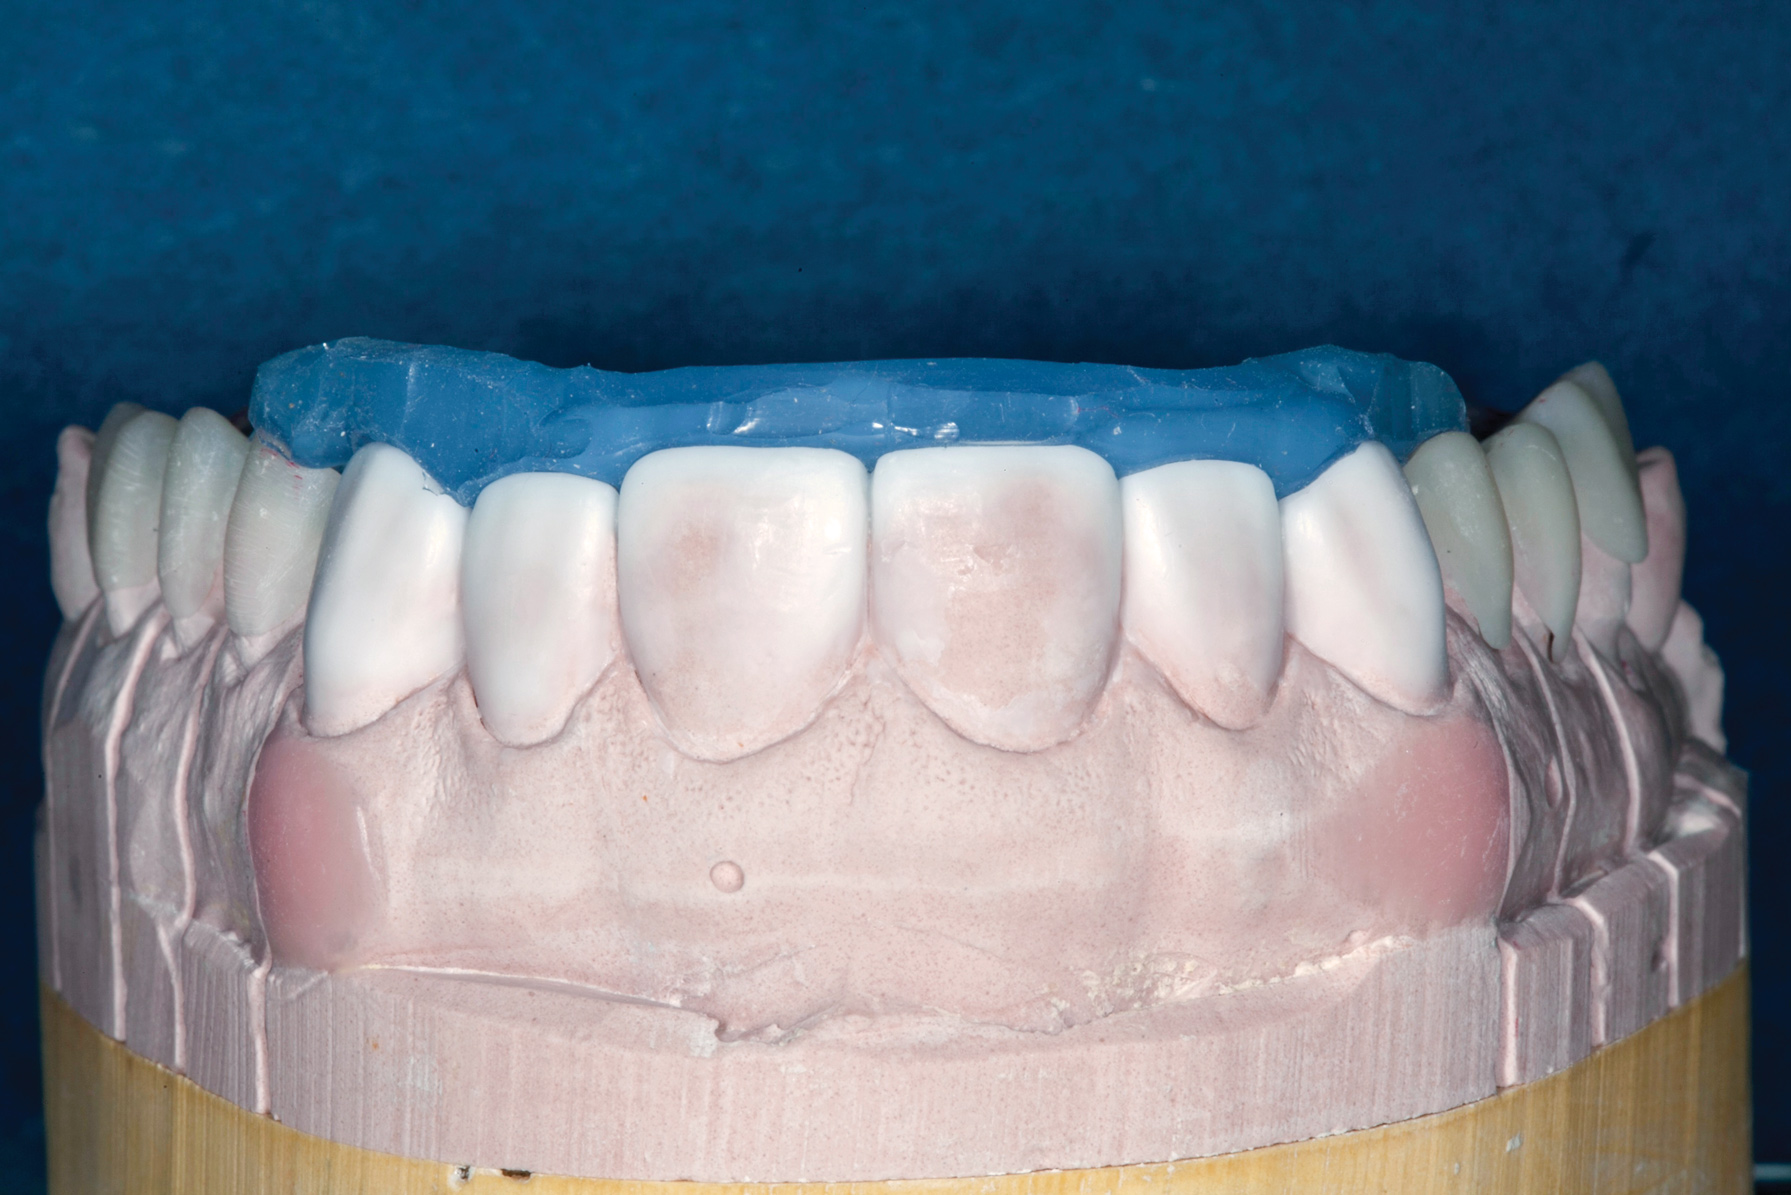

(13.) Postoperative occlusal view of upper arch.

Figure 13

Treatment

Accurate vinyl polysiloxane impressions were taken of the upper and lower arches. Two sets of models were obtained and mounted in a semi-adjustable articulator. A diagnostic wax-up to close the posterior open spaces and incorporate the desired esthetic changes was carried out on one of these sets. The posterior waxed-up surfaces were then duplicated with a clear silicon matrix in quadrants. These matrices were loaded with a slightly warmed microhybrid composite and seated onto the corresponding second model, which had been isolated with a separating agent. Warming composites increases monomer conversion, thereby decreasing curing time and shrinkage.18 Once fully cured, the occlusion was adjusted, and the onlays could easily be separated from the models.